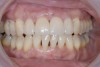

A patient in her 60s wanted to improve her smile but declined orthodontic treatment in favor of porcelain veneers (Figure 13). However, addressing her 8-mm pocket was the first step. The practitioner created biologically clean root surfaces using ultrasonic open-flap debridement, finishing burs, and manual tool instrumentation. Next, a mineralized freeze-dried bone allograft saturated in platelet-derived growth factor (Figure 14) using chemotaxis pulled the stem cells capable of regeneration into the site where repopulation was needed. Prior to closure, a resorbable membrane, polylactic acid-guided tissue regeneration—known for periodontal regeneration—was used (Figure 15). At 10 weeks, adequate healing had occurred. The patient at 6 and 10 weeks showed continued healing. Although some postoperative recession was evident, probing depths were less than 2 mm, and the patient was referred back to the restorative dentist for restorative therapy. As of this writing, she has not lost any teeth and is periodontally stable (Figure 16).

Figure 15

The final restorative situation. (Restorative therapy by Dr. B. Wilk, Chalfont, PA.)